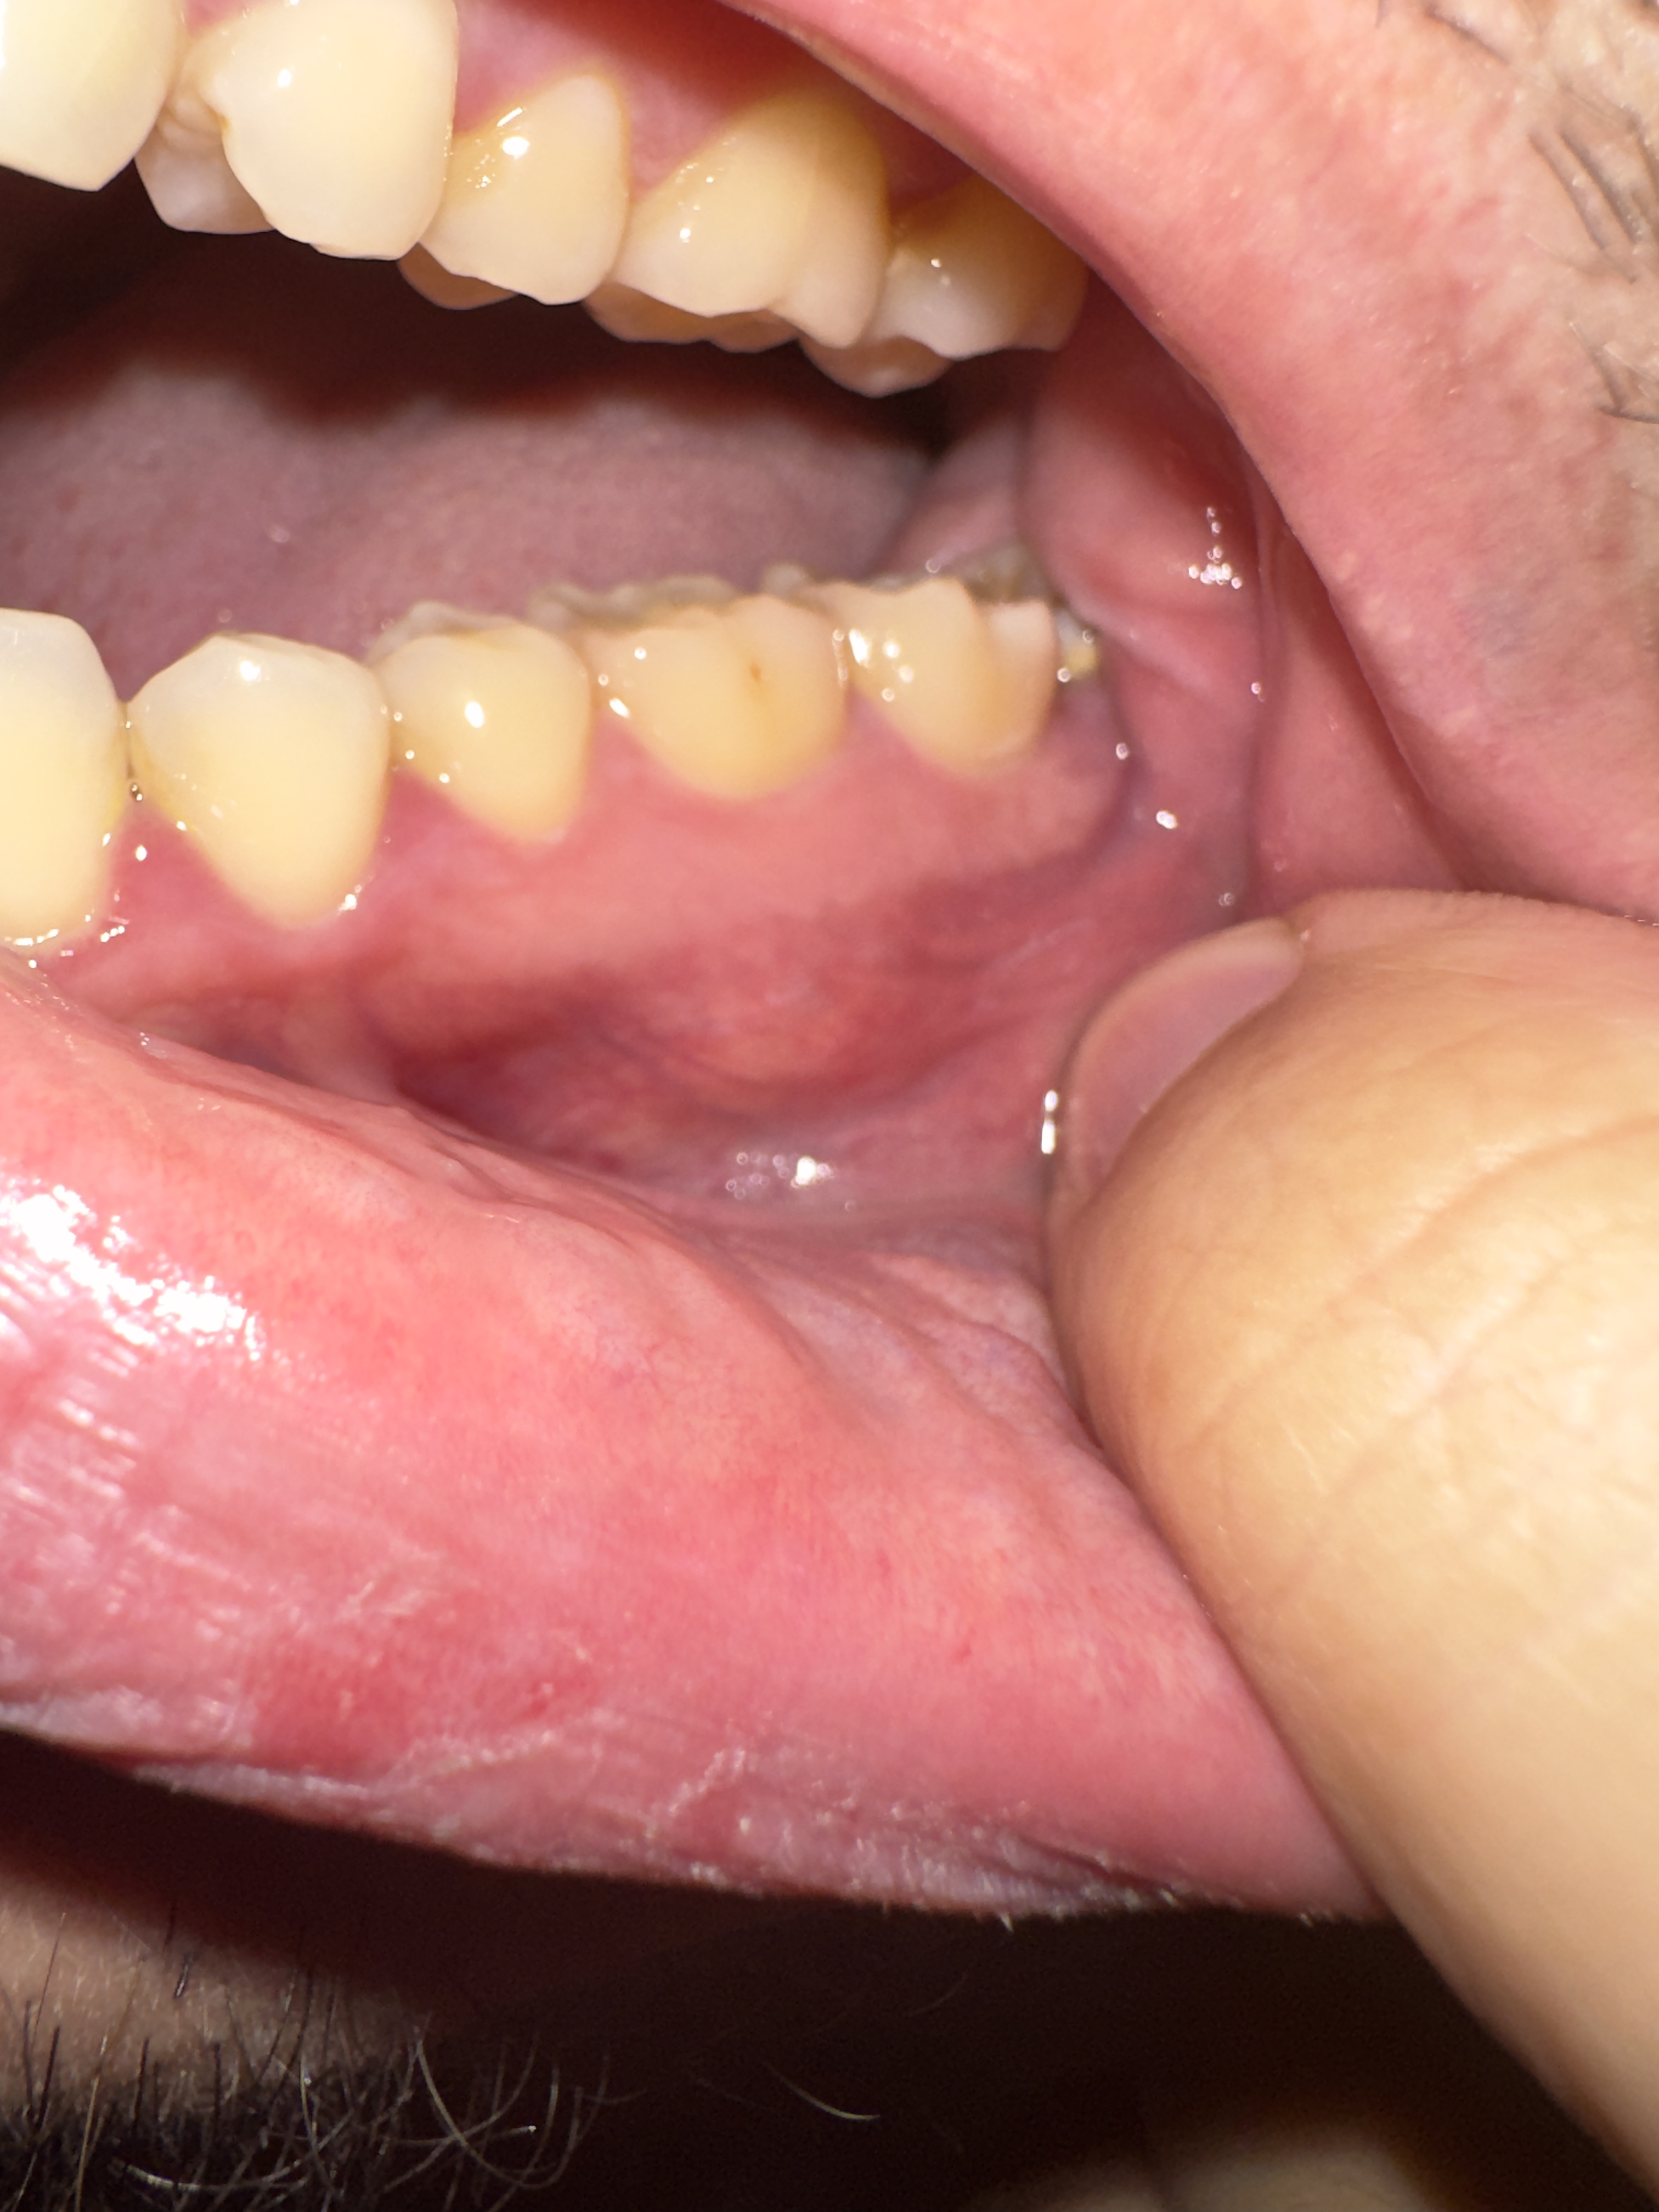

Hallo Tandarts Forum. Ik heb hard pijnloze bultje bij mijn tandvlees bij de kaak.. Ik vroeg mij af wat het kan zijn.. abces of cyste of onsteking..? zie ik meerendeels op internet voorbij komen. Ben al een hele lange tijd niet naar de tandarts geweest omdat ik nogal bang ben voor de tandarts, wat vroeger eigenlijk niet zo was.. Met vriendelijke groet!